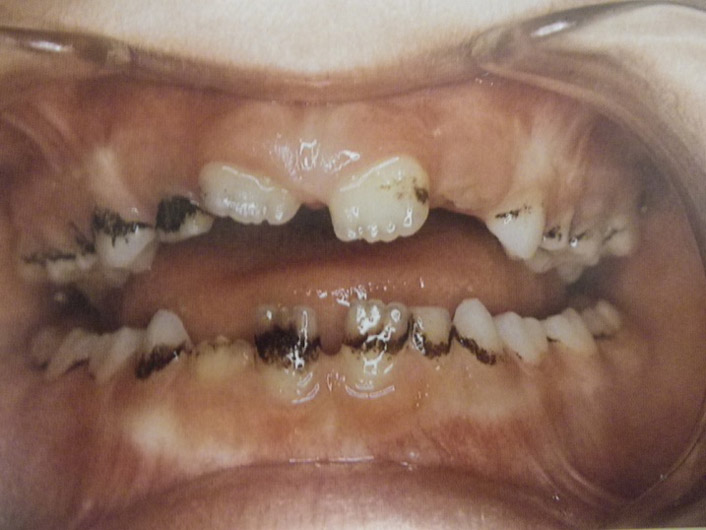

Τερηδόνα βρεφικής και νηπιακής ηλικίας ή τερηδόνα θηλασμού

Η τερηδόνα βρεφικής και νηπιακής ηλικίας εμφανίζεται σε μικρά παιδιά ηλικίας 2 έως 5 ετών, τα οποία έχουν τερηδονισμένα ένα ή και περισσότερα νεογιλά δόντια. Η τερηδόνα αυτής της μορφής οφείλεται σε λάθος τρόπο διατροφής του παιδιού και μπορεί να εξελιχθεί γρήγορα και σε μεγάλη έκταση επηρεάζοντας το σύνολο το δοντιών που βρίσκονται στο στόμα.

Η κυριότερη αιτία εμφάνισης της τερηδόνας αυτής της μορφής είναι το τάισμα με το μπιμπερό ενώ το παιδί κοιμάται. Κατά τη διάρκεια του ύπνου η ποσότητα του σάλιου μειώνεται και το γάλα, ανεξάρτητα αν περιέχει ή όχι ζάχαρη, παραμένει πάνω στα δόντια και προκαλεί τερηδόνα. Ακόμη και το μητρικό γάλα μπορεί να έχει τις ίδιες συνέπειες, εφόσον το παιδί θηλάζει κατά βούληση κατά τη διάρκεια της νύχτας.

- Η τερηδόνα των νεογιλών δοντιών προκαλεί πόνο και μερικές φορές πυρετό και κακουχία στο παιδί, καταστάσεις δυσάρεστες τις οποίες κανένας γονιός δεν θα ήθελε να βιώσει το παιδί του.

- Η παρουσία τερηδονισμένων νεογιλών δοντιών μπορεί να επηρεάσει και τα μόνιμα δόντια, διότι η τερηδόνα οφείλεται στα μικρόβια τα οποία μεταδίδονται με το σάλιο από δόντι σε δόντι. Εφόσον το περιβάλλον της στοματικής κοιλότητας που αναπτύσσονται τα μόνιμα δόντια δεν είναι υγιές, τότε είναι θέμα χρόνου να "χαλάσουν" και αυτά.